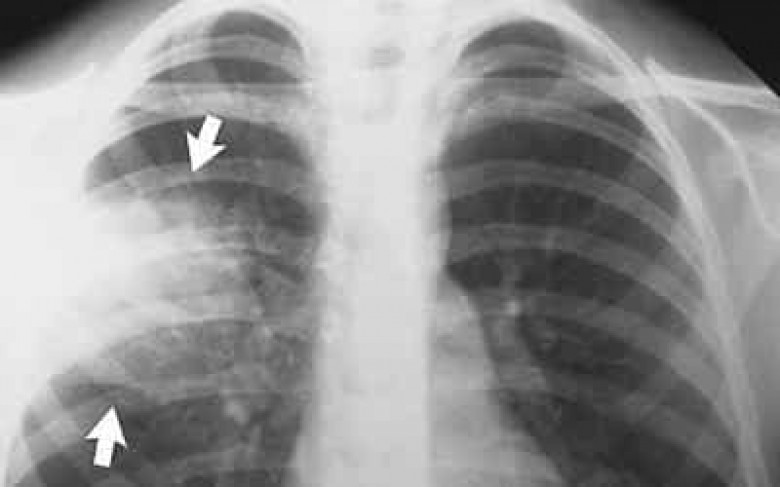

ՀԱՍԱՐԱԿՈՒԹՅՈՒՆՀանրապետությունում վերջին օրերի ընթացքում սուր շնչառական խնդիրներով հոսպիտալացվել է 24 հղի կին, որոնցից 5-ի մոտ ախտորոշվել է թոքաբորբ: Այս մասին այսօր՝ դեկտեմբերի 5-ին, կառավարությունում տեղի ունեցած խորհրդակցության ժամանակ հայտարարել է Առողջապահության նախարար Արմեն Մուրադյանը։

Կառավարությունից NEWS.am-ին հայտնում են, որ ըստ նախարար Մուրադյանի, նրանցից 2-ը ներկայում գտնվում են վերակենդանացման բաժանմունքում և նրանց վիճակը ևս աստիճանաբար բարելավվում է:

Ցավոք, գրանցվել է թոքաբորբով հիվանդ մեկ հղի կնոջ մահվան դեպք, ինչը, նախարարի զեկուցմամբ, պայմանավորված է եղել հիվանդության կտրուկ սրմամբ և բժիշկներին ուշ դիմելու հանգամանքով: Դեպքի առնչությամբ պատրաստվում են քննչական նյութեր: Արմեն Մուրադյանը նշել է, որ բոլոր հիվանդների վիճակն ուժեղացված կերպով վերահսկվում է: